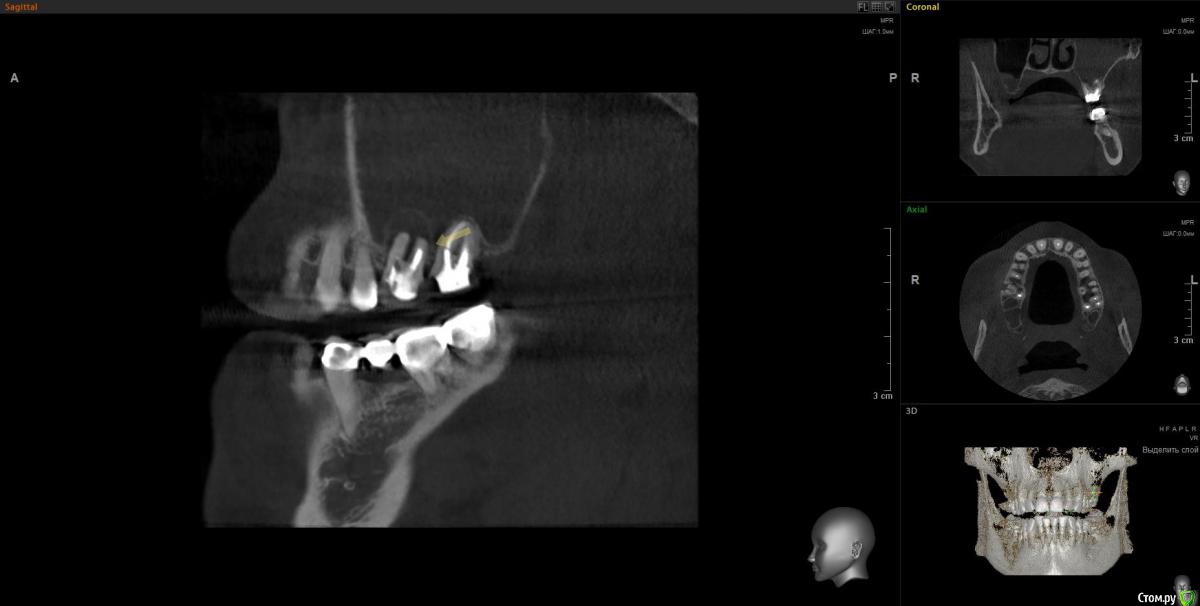

Doctor Vlad Опубликовано 14 апреля, 2020 Автор Поделиться Опубликовано 14 апреля, 2020 А дальнейшие планы каковы? Просто санация либо планируется реконструкция?Очень в тему вопрос. На работе задумался- а что дальше? и проблемка стала шире... как раз кт скинули. Там же не просто зашить и забыть там 2 импланта нужны)Кт до удаления месяца 2 назад. Стрелочка место где виднелась слизистая пазухи в момент удаления. по моим расчетам можно было бы без синуса если вся полость кисты заполнится костью, но теперь там будет скорей всего тяж или клапан этот. киста сама дно синуса приподняла. Ссылка на комментарий

Doctor Vlad Опубликовано 14 апреля, 2020 Автор Поделиться Опубликовано 14 апреля, 2020 Снимок до Ссылка на комментарий

Doctor Vlad Опубликовано 24 сентября, 2020 Автор Поделиться Опубликовано 24 сентября, 2020 27 удалил месяцев 3 назад, отмыл пазуху, зашил все заплаткой сст. сообщение закрылось. снимок кт свежий. хочу 2 импланта туда поставить. дефект костный дна синуса ламиной закрыть на винтах. все равно слой своей кости не велик, стружка понадобится. какие будут мнения? Ссылка на комментарий

Doctor Vlad Опубликовано 24 сентября, 2020 Автор Поделиться Опубликовано 24 сентября, 2020 (изменено) Самое главное забыл. кт свежее! и снимок на этапе зашивания соустья удаления 27 Изменено 24 сентября, 2020 пользователем Doctor Vlad Ссылка на комментарий

kriokov Опубликовано 24 сентября, 2020 Поделиться Опубликовано 24 сентября, 2020 какие будут мнения? клкт свежее сделайте, может там без лишней оротьбы обойдется-- синус и два болта, Ссылка на комментарий